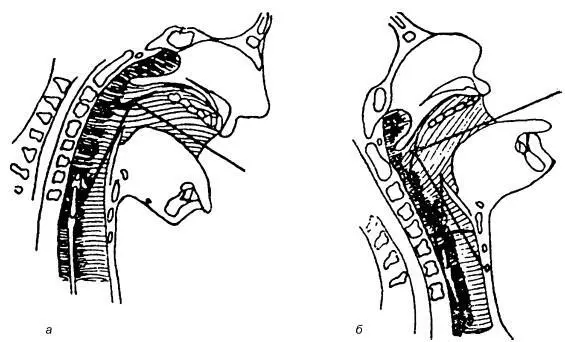

Поскольку при непрямой ларингоскопии осмотр гортани возможен только одним левым глазом, т. е. монокулярно (в чем легко убедиться при его закрытии), то все элементы гортани видны в одной плоскости, хотя голосовые складки располагаются на 3–4 см ниже края надгортанника. Боковые стенки гортани визуализируются резко укороченными и как бы в профиль. Сверху, т. е. фактически спереди, видна часть корня языка с язычной миндалиной (см. рис. 19.2, 1), затем бледно-розовый надгортанник ( 2), свободный край которого при фонации звука «и» поднимается, освобождая для обозрения полость гортани. Непосредственно под надгортанником в центре его края иногда можно увидеть небольшой бугорок (3) – tuberculum epiglotticum, образованный ножкой надгортанника. Ниже и кзади надгортанника, расходясь от угла щитовидного хряща и комиссуры к черпаловидным хрящам, расположены голосовые складки (7) белесовато-перламутрового цвета, легко идентифицирующиеся по характерным трепетным движениям, чутко реагирующие даже на незначительную попытку фонации. Во время спокойного дыхания просвет гортани имеет вид равнобедренного треугольника, боковые стороны которого представлены голосовыми складками, вершина как бы упирается в надгортанник и часто им прикрыта. Надгортанник является препятствием для осмотра передней стенки гортани. Для преодоления этого препятствия применяют позицию Тюрка, в которой осматриваемый запрокидывает голову, а врач проводит непрямую ларингоскопию стоя, как бы сверху вниз (рис. 19.4, б). Для лучшего обзора задних отделов гортани применяют позицию Киллиана, при которой врач осматривает гортань снизу (стоя на одном колене перед больным), а больной наклоняет голову книзу (а).

Рис. 19.4.Направление хода лучей и оси зрения при непрямой ларингоскопии в позиции Киллиана (а) и Тюрка (б)